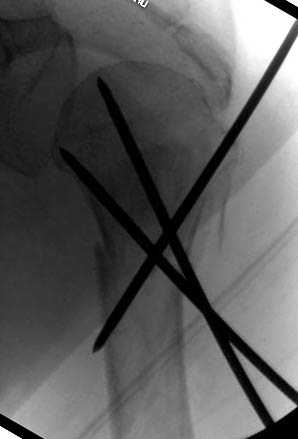

Наш недавний случай перкутанной фиксации "методом

Сиэтла" спицами 2.8 мм с резьбой на конце.

Наличие рентген контроля (ЭОП) помогает во время

репозиции и фиксации, но многие коллеги умудряются без рентгена фиксировать несколькими спицами перкутанно.

Из-за тенденции миграции осторожно со спицами,

особенно у пожилых, слабые кости не выдерживают

нагрузку, были случаи миграции, обнаруженные при первом же амбулаторном приеме, поэтому методика Лазарева напряженными спицами более приемлема, особенно у тех, кто испытывает нехватку фиксирующих конструкций (на сайте

имеется описание техники).